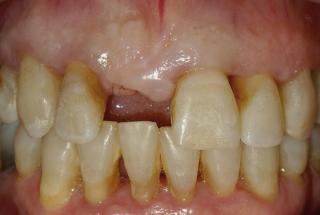

Clinical cases

MPI closely monitors clinical cases in the market to ensure their correct functioning and successful outcome.